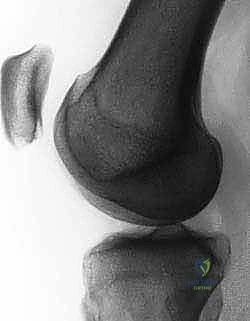

Pre-Operative Planning, Templating, and Patient Positioning

Thorough preoperative planning is the roadmap to a successful surgical outcome. The process begins with a meticulous review of high-quality imaging. Standard plain radiographs are mandatory and must include a standing anteroposterior (AP) view, a true lateral view taken at exactly 30 degrees of knee flexion, and an axial (Merchant or sunrise) view at 30 to 45 degrees of flexion. On the true lateral radiograph, we meticulously assess for trochlear dysplasia by looking for the "crossing sign," where the floor of the trochlea intersects the anterior borders of the femoral condyles.

We also quantify the trochlear prominence; a measurement of 3 mm or greater is highly indicative of dysplasia that may compromise isolated soft-tissue procedures.

The lateral view is also utilized to calculate the Caton-Deschamps ratio to rule out significant patella alta.

Advanced cross-sectional imaging, specifically MRI and occasionally CT, is indispensable. Axial CT or MRI is used to accurately measure the TT-TG offset, ensuring it falls within the acceptable range (< 15-20 mm) for an isolated MPFL procedure.

However, MRI is the primary modality for evaluating the soft-tissue envelope. We scrutinize the T2-weighted axial and coronal sequences to identify the exact location of the MPFL failure. We look for the classic "wavy" appearance of a detached ligament, surrounding edema, and the presence of a distinct stump at the patellar margin.

Crucially, the MRI must be reviewed for concomitant articular cartilage damage; osteochondral loose bodies originating from the medial patellar facet or the lateral femoral condyle are common and must be addressed concurrently.